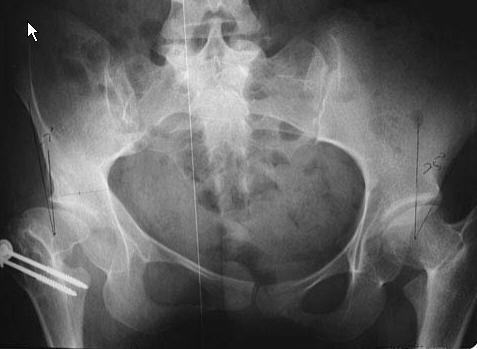

? correct pelvic osteotomy ?

Chiari or Shelf (salvage for unreducible head)

both depends on fibrocartilge metaplasia for successful results